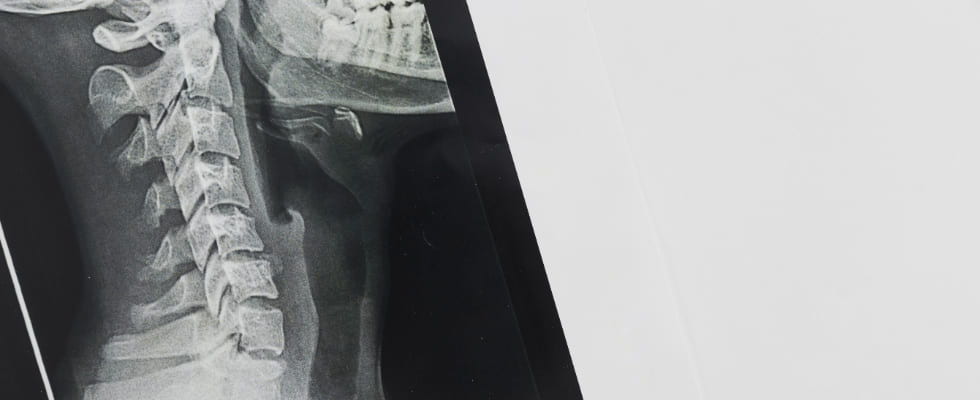

Radiografía de cuello

La radiografía de cuello es una técnica de diagnóstico por imagen que utiliza rayos X para obtener imágenes detalladas de las estructuras internas del cuello, incluyendo huesos, tejidos blandos y órganos. Esta prueba identifica y evalúa diversas condiciones médicas, como fracturas, infecciones, tumores y problemas en las vías respiratorias o el esófago.